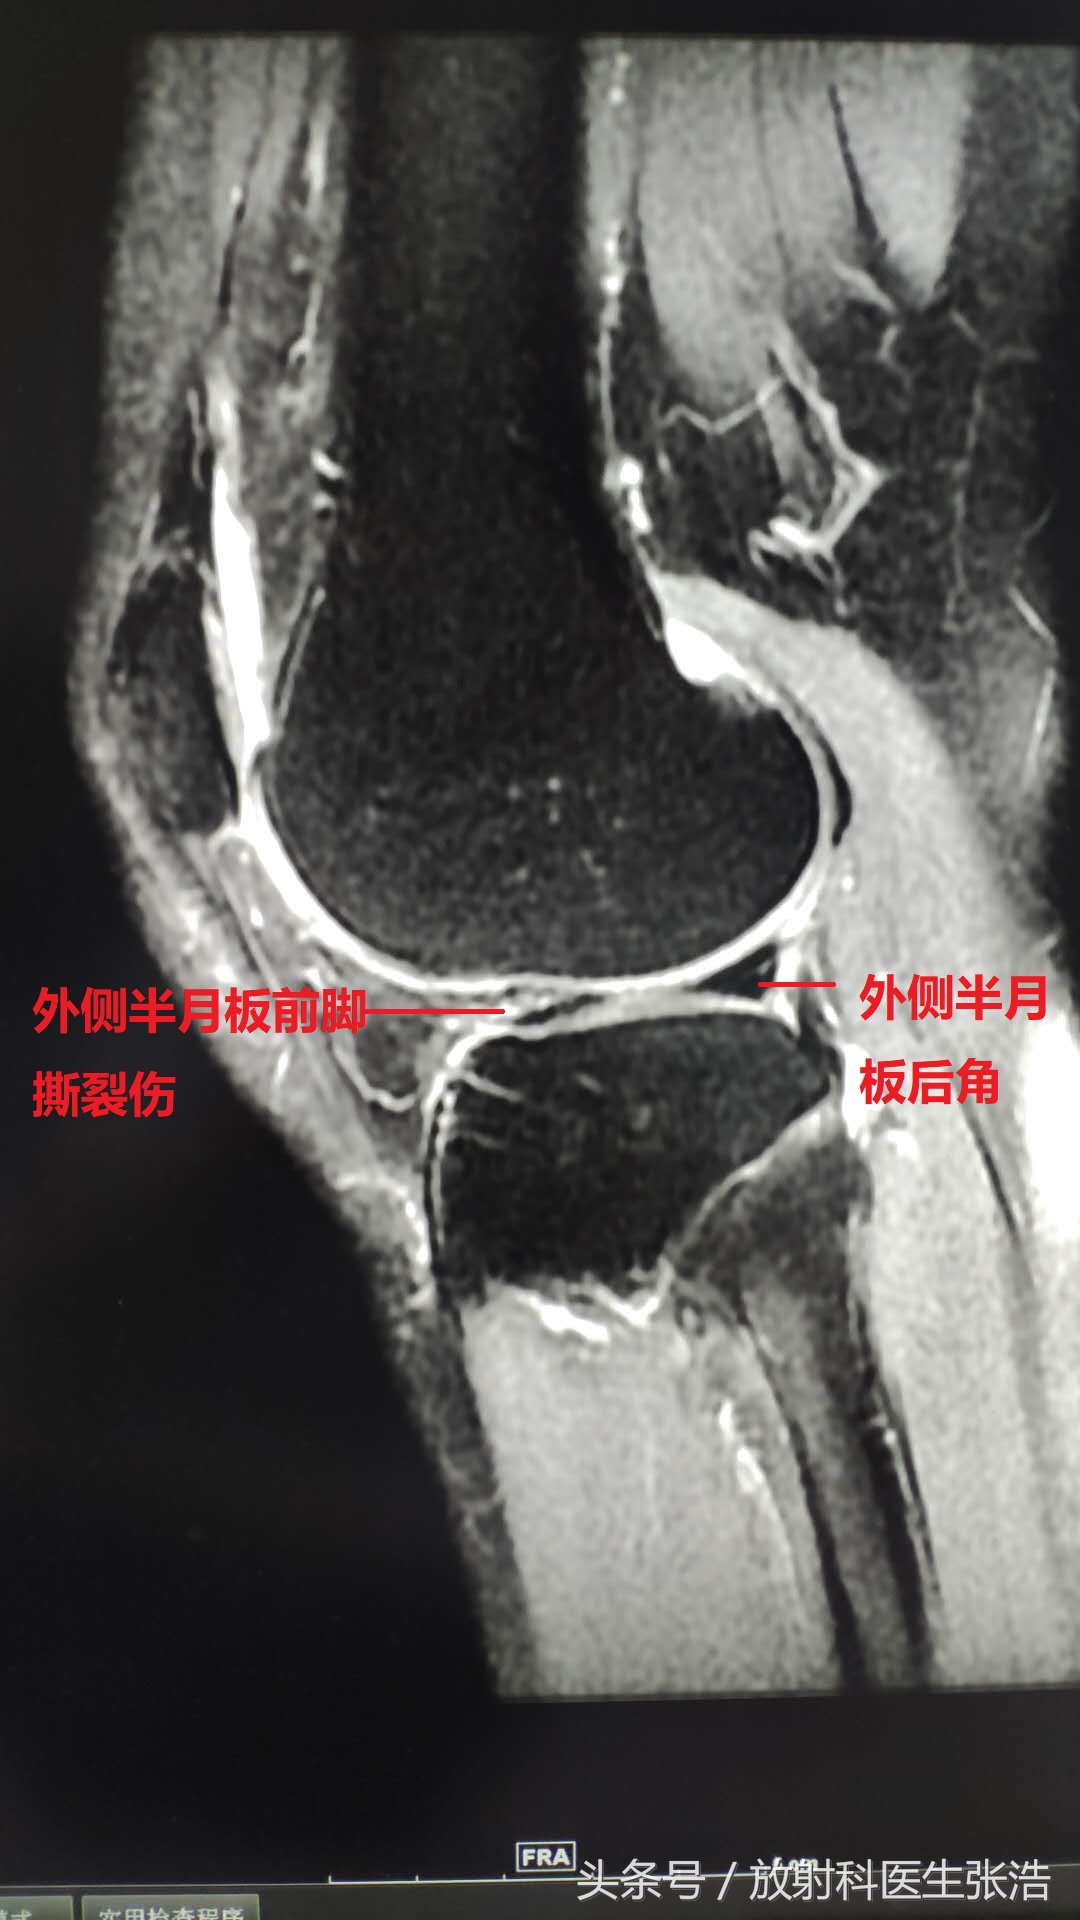

4、最后一张就是之前提到的半月板损伤了,半月板是膝关节连接股骨和胫骨重要的纤维软骨结构(就是平时说到的脆骨),一旦出现损伤或者磨损将直接影响膝关节的活动,并且磨损疼痛的厉害。西面就可以看到半月板前角因为外伤出现了撕裂伤,需要技师手术治疗的。